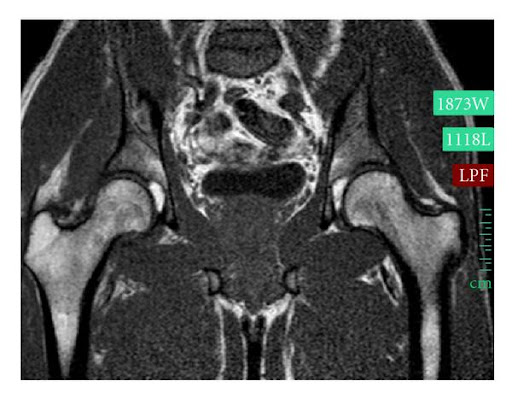

Chụp X-quang tại chỗ cho thấy khớp hông đã trở về đúng vị trí. Quá trình thực hiện thủ thuật không gặp khó khăn. X-quang được chụp một tuần sau thủ thuật cho thấy khớp háng phải đúng vị trí và không có dấu hiệu gãy xương (Hình 2). MRI được thực hiện một tuần sau đó cho thấy không có tràn dịch khớp háng phải nhưng có rách dây chằng tròn và tràn dịch khớp háng. Không thể phát hiện tổn thương sụn viền (Hình 3).

Hình ảnh MRI khớp háng hai bên. Có hình ảnh sưng nề các cơ chậu bên phải